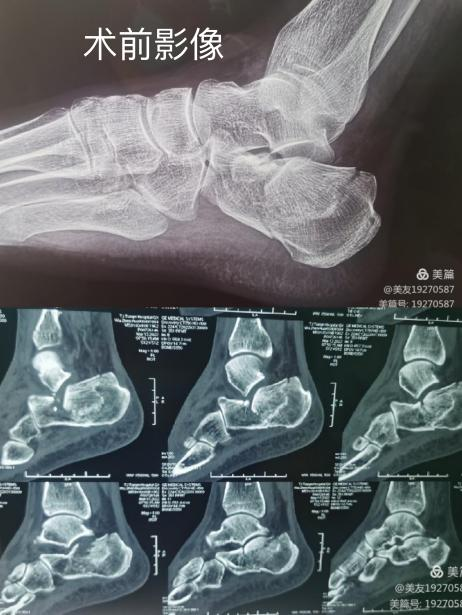

只打几个直径0.5厘米的小孔,就能顺利完成跟骨骨折手术?很多人想象中不可能的事,通辽市医院做到了。近日,我院骨二科张继峰团队为一位Sanders II型跟骨骨折患者成功开展跟骨骨折闭合复位“钉中钉”微创固定系统内固定术,在复位良好的基础上,达到了微创治疗的目的。该手术方式在我院率先开展,标志着我院骨科专业水平再上新台阶!

患者武某某,摔伤8天,双足跟部疼痛、肿胀、不能行走,入我院诊断为双足跟骨骨折,张继锋主任医师组织术前讨论,制定治疗方案,给予手术治疗,在腰硬联合麻醉下由单德龙主任医师和陈立福副主任医师给予患者右侧跟骨骨折闭合复位,使用跟骨钉中钉内固定新技术手术治疗,因为是微创手术,术后患者恢复很快,术后3天患者出院,足踝关节功能良好,患者满意度高。